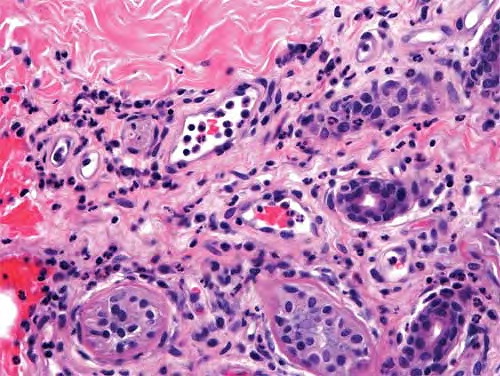

Idiopathic recurrent palmoplantar hidradenitis = التهاب الغدد العرقية الراحي الاخمصي الناكس ومجهول السبب